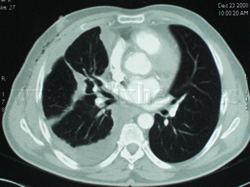

Mesotelioma pleural

Estudios de imagen